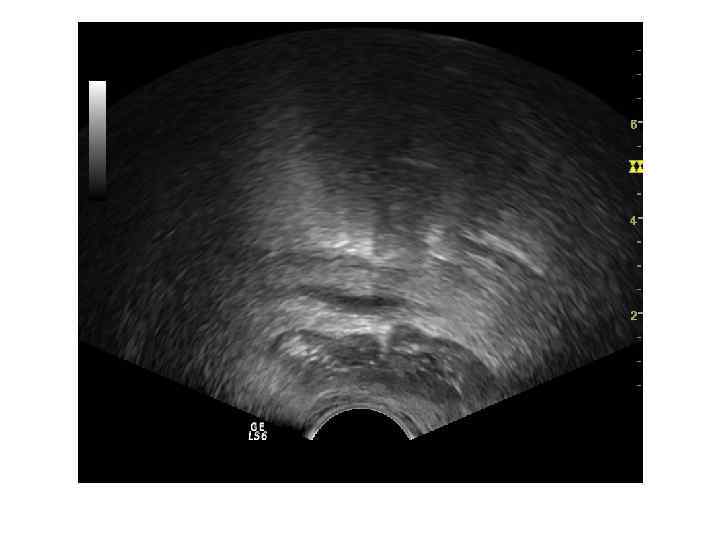

Острый простатит Острое воспалительное заболевание предстательной железы, при котором можем увидеть сонографически несколько основных признаков: - умеренное диффузное увеличение объема железы - однородность структуры железы; - наличие диффузного снижения эхогенности преимущественно в периферической части железы. - изменение семенных пузырьков в виде их асимметрии и расширение семявыбрасывающих протоков на фоне возможного блока. - умеренное расширение вен парапростатического сплетения В режиме ЦДК: симметричное и равномерное обогащение сосудистого рисунка.

Хронический простатит характеризуется полиморфизмом картины. Различают 4 формы: -отёчная – диффузное увеличение размеров и чередование зон повышенной и пониженной эхогенности с преобладанием гипоэхогенности. -конгестивная (застойная) - диффузная неоднородность структуры - чередование зон повышенной и пониженной эхогенности, отмечается более выраженная дифферецировка анатомо-функциональных зон. Размер железы может быть незначительно увеличен. -калькулёзная - присутствие гиперэхогенных включений чаще без акустической тени. -склеротическая - при которой преобладает диффузное повышение эхогенности и уменьшение размеров.